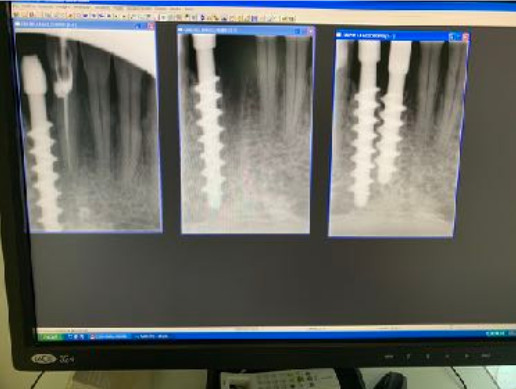

Tipo di impianto

Tramonte

App.Rx endorale

VixWin Guidizzolo

Tac

presente

Situaz.estrattiva

postestrattivo immediato

Densità secondo Misch

D2